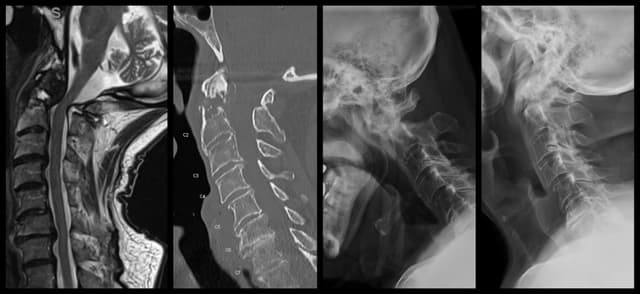

C1-2 Fusion

Imaging